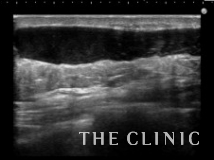

悪性腫瘍と違い、脂肪によるしこりの癒着はほとんどが剥離することができます。

乳輪切開でしこりを除去しました。

大きなしこりを摘出した場合は、スペースが大きいためリンパ液や血液が貯留する場合がありますが、この方も1週間後の診察で少量の血液とリンパ液が溜っていましたが、注射針で吸引して消失しました。